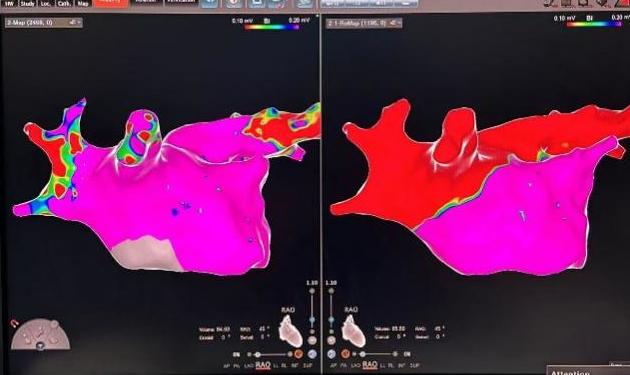

周某,78岁,长期受到持续性房颤的困扰,合并冠心病、高血压,并有一次卒中史,病程长达十余年。起初,症状表现为偶发的心悸和胸闷,但近几年症状逐渐加重,发展为频繁气短、乏力,严重影响了日常生活。考虑到他的卒中史以及房颤带来的潜在风险,且曾因心脏功能异常植入过起搏器,周爷爷的治疗方案在兰州大学第一医院心血管团队的精心制定下,采取了个性化的综合治疗方案,不仅通过先进的脉冲消融术精准处理房颤,还结合其卒中风险高的特点,施行了经皮左心耳封堵术,从源头预防卒中发生,为患者提供全方位保护。这一双管齐下的治疗策略,不仅显著改善了心律失常,还为患者的未来健康筑起了一道坚实的屏障。

FARAPULSE导管花瓣消融

左心耳封堵器完美封堵

房颤是临床上最常见的心律失常之一, 随着治疗手段的不断进步,房颤的治疗目前已进入一个新的阶段,脉冲消融是利用高电压脉冲电场作用于心腔内组织,心肌细胞膜磷脂双分子在脉冲电场作用下发生移动,并重新排列,形成不可逆电穿孔,进而使细胞凋亡,达到消除及阻止异常电位传递的目的。相比射频消融脉冲消融具有以下优势:①具有组织选择性,不易损伤毗邻组织;②非热能的消融方式,安全性提升;③手术时间缩短,放电时间短,每次放电仅需2.5秒。手术使用的FARAPULSE一次性心脏脉冲消融导管,是全球首个上市的脉冲消融技术,其安全性和有效性拥有全球最多的临床研究数据支持。每台手术消融时间平均在30分钟,相较其他消融方式,极大提升手术效率,更好地让患者获益。